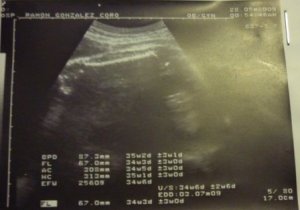

Fotos del 28 de mayo de 2009 (32 semanas):

Informe:

Feto único

Diámetro Bi-Parietal [DBP]: 87.3 mm, corresponde a la talla de 35s2d ± 3s

Longitud del Fémur (LF): 67 mm, corresponde a la talla de 34s5d ± 3s

Circunferencia Abdominal [CA]: 308 mm, corresponde a la talla de 34s5d ± 3s

Circunferencia craneal (CC): 313 mm, corresponde a la talla de 35s2d ± 3s

Peso estimado: 2 560 gramos, corresponde a la talla de 34s6d ± 3s

Latidos Cardiacos [LC]: Normal

Movimientos Respiratorios [MR]: Presentes

Conclusión: Auril es GRAAAAANDEEEEEE. Pobrecita yo… 😦